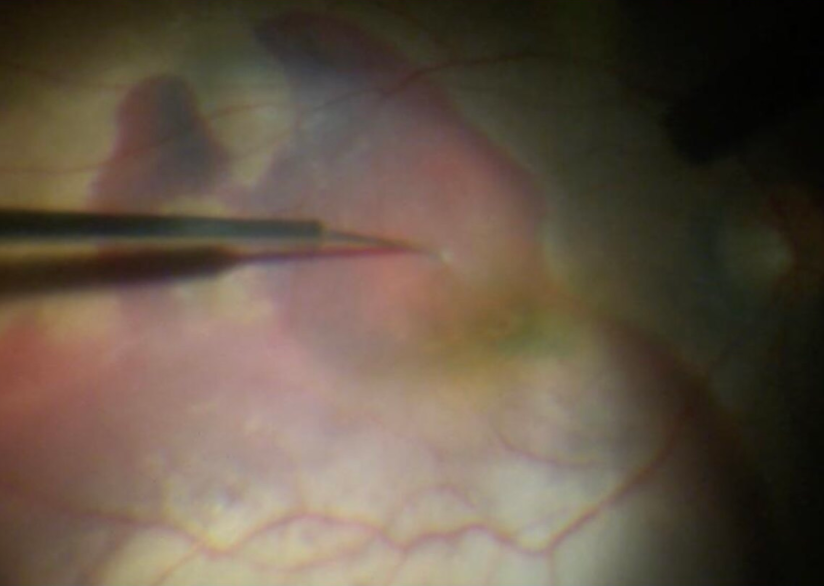

胡志翔医师介绍,温医大眼视光医院吴荣瀚教授早在 2010 年开展了针对